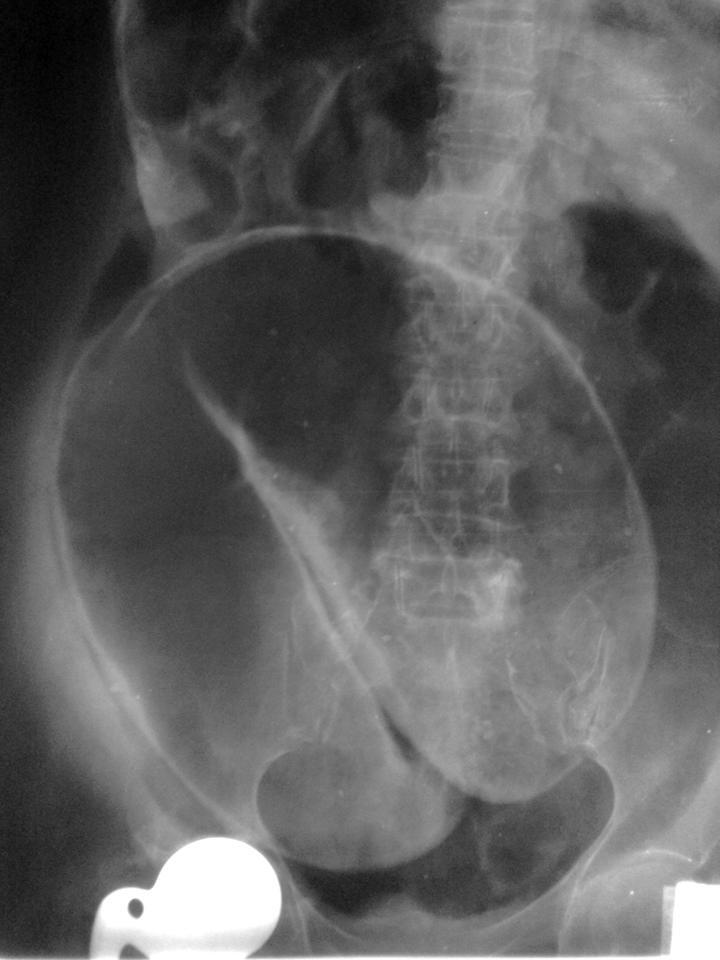

11

Q

what does this AXR show?

A

sigmoid volvulus

- coffee bean sign

- dilation of proximal large bowel

- rigler’s sign (both sides of bowel visible) if perforation has occurred